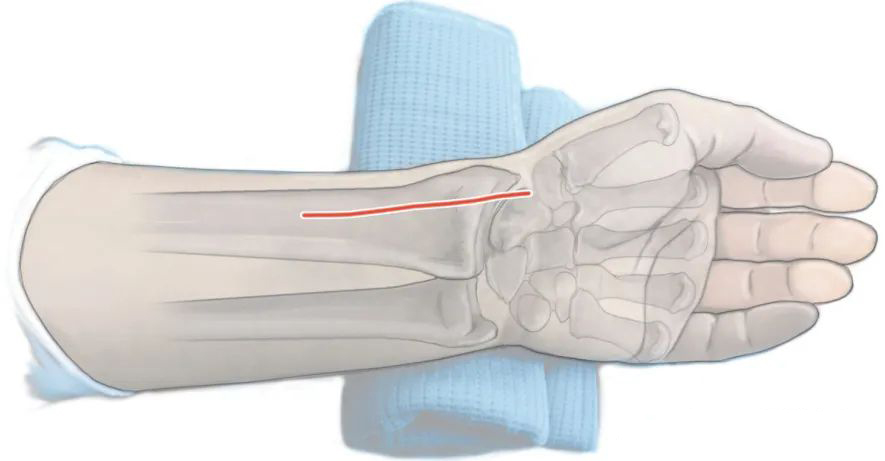

Схематическая диаграмма положения лежа на спине (Источник: «Принципы лечения переломов АО» (3-е издание)).

Пораженная конечность отведена, а поле зрения может быть изменено за счет пронации и супинации (Источник: DOI: 10.1007/s00064-023-00818-6).